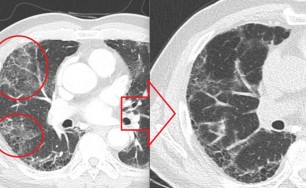

이런 형태의 기침은 엑스레이상 정상인 경우가 대부분입니다.

원인은 기도의 광범위한 상피세포의 손상과 탈락입니다.

기도의 상피세포가 손상을 받으면 점액 섬모의 청소장애가 나타나 기침을 유발합니다.

숨케어한의원에서는 전화예약을 받고 있습니다. 내원시 엑스레이, CT사진, 폐기능검사지를 가지고 오시면 자세한 상담이 가능합니다.